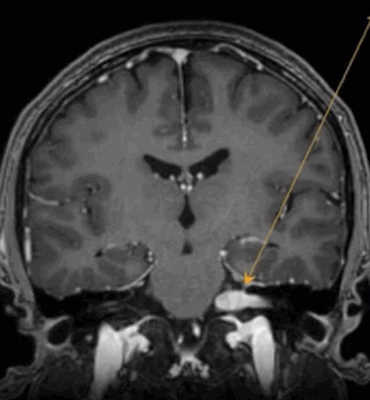

МРТ головного мозга. Т1-взваешенная МРТ с контрастированием. Менингиоангиоматоз.